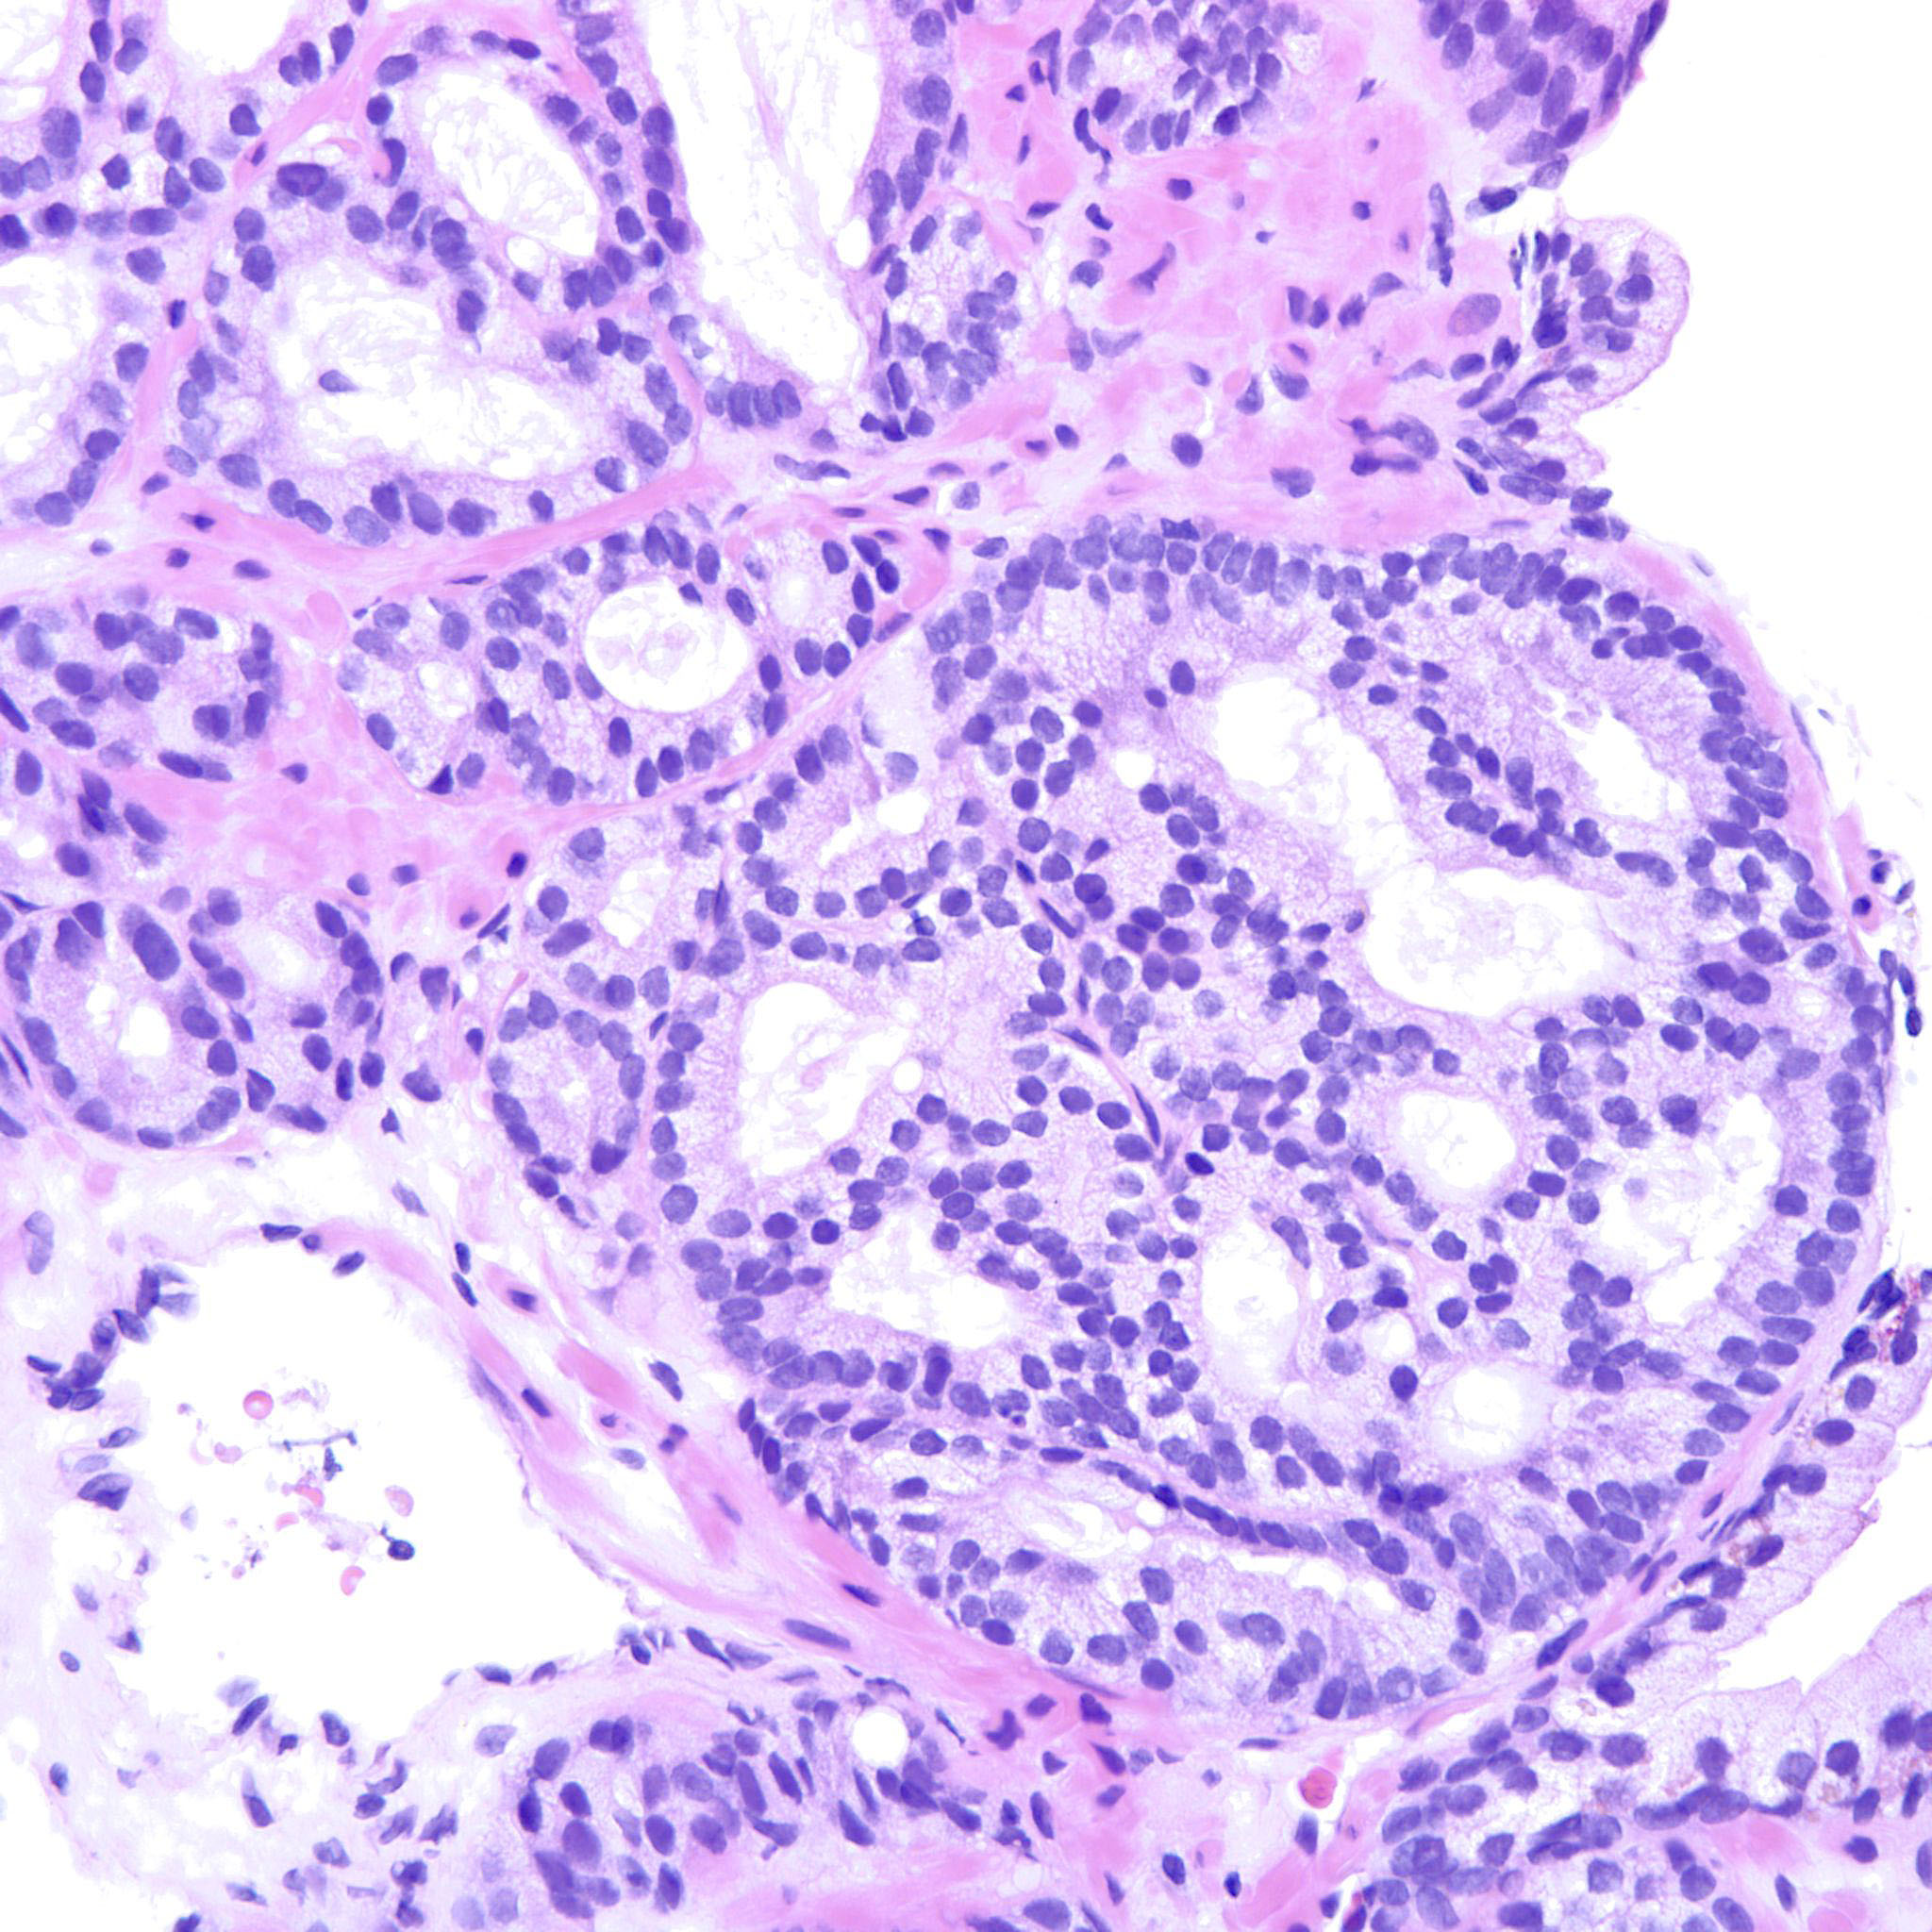

Prostate cancer grading

Case ID: 188